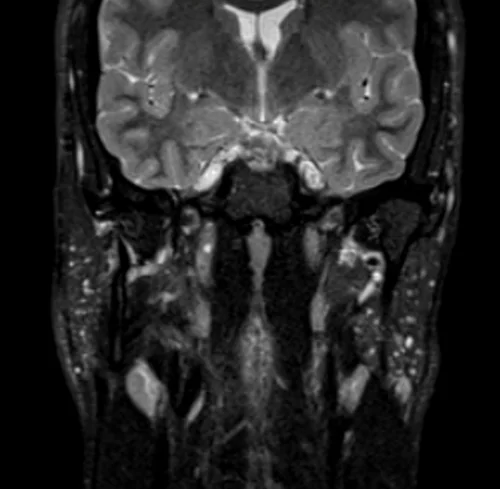

MRI face STIR coronal images